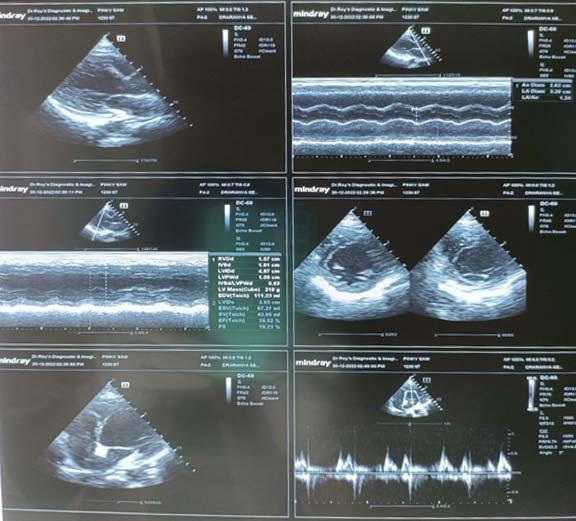

The vaccination status of the subjects in which only 26 participants had been vaccinated which contributes

only 11.5% of the total study population (Fig 1). The severity of the COVID infection in which the majority (42%) had the moderate form of the disease and only 24.4% had a severe form of the disease (Fig 2).

Fig 1 — Vaccination status of study subjects (N-226)